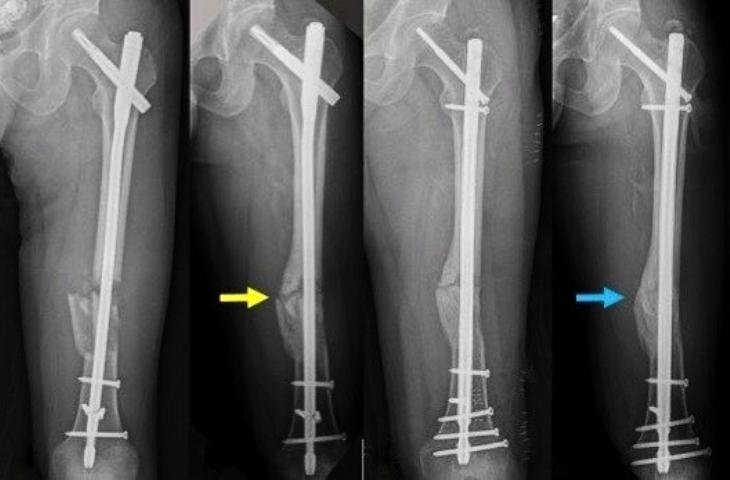

Đối với các trường hợp gãy xương thông thường, nếu sức khỏe người bệnh vẫn được đảm bảo thì việc đi máy bay là vô cùng bình thường. Nhưng đối với người gãy xương bắt vít có đi máy bay được không là thắc mắc của khá nhiều người. Thực ra, chân bạn khi bắt vít vẫn có thể đi máy bay được nếu bác sĩ khuyến nghị.

Do tùy thuộc vào tình trạng và vị trí khi bắt vít, bạn sẽ có có thể khó di chuyển hơn. Nên cần thực hiện các kiểm tra và tham khảo thêm ý kiến của bác sĩ để có thể sắp xếp chuyến đi một cách tốt nhất.

Trong trường hợp bạn vừa mới bắt vít hay có khả năng vết thương bị chảy máu hay sưng mủ thì cần cân nhắc hơn về tình trạng sức khỏe của bản thân trước khi bắt đầu chuyến đi.